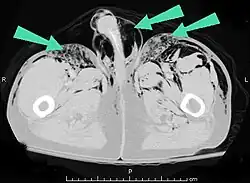

Subcutaneous air (arrows) can be seen as black areas on this pelvic CT scan.